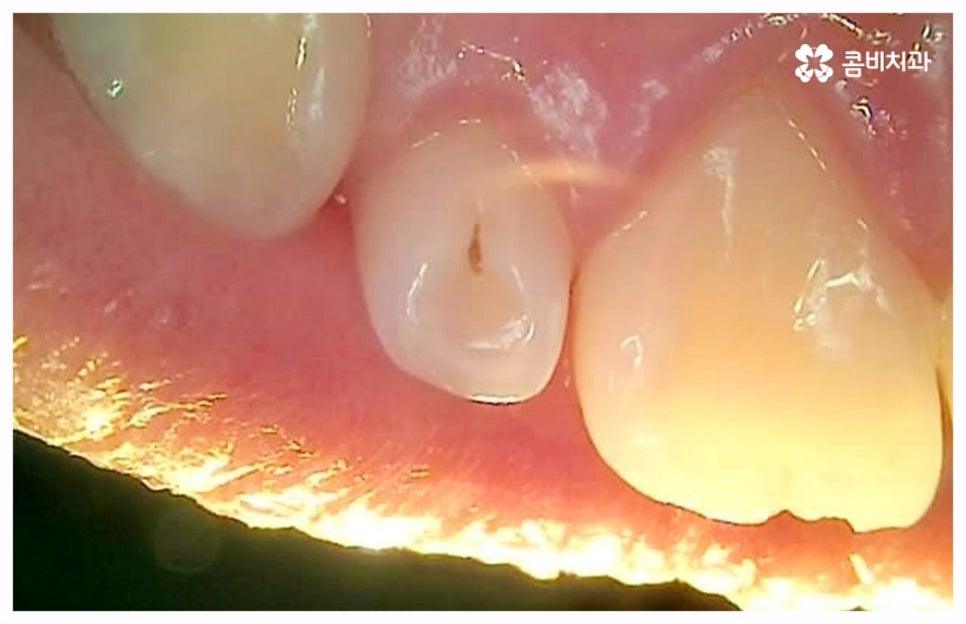

출처 아카이브 열기치통의 원인은 굉장히 다양한데 그 중 가장 대표적인 것으로는 구강 질환과 치아파절을 생각해 볼 수 있을 거예요. 충치나 잇몸병과 같이 구강 내부 상황으로 인해 발생하는 것이 구강 질환이라면 외부에서 충격을 받아 치아가 부러지거나 깨지는 것을 치아파절 이라고 할 수 있는데요. 이렇게 내적 또는 외적인 원인으로 생긴 치아 손상은 자연적으로 낫지 않으며 시간이 지날수록 빠르게 악화되기 때문에 구강 질환이 발생했거나 치아가 파절되었을 때 시기를 늦추지 말고 바로 치과에 내원하셔서 꼼꼼하게 검진을 받고 상황에 적합한 치료를 받으실 필요가 있습니다.

충치나 잇몸 질환은 보통 단계적으로 서서히 발전하기 때문에 환자분들께서 하루 아침에 극심한 통증을 느끼게 되는 경우는 많지 않지만 혹시라도 갑작스럽게 치통이 심할때 혹은 밤에 자려고 누웠는데 더욱 치통이 심할때 는 급성치수염을 의심해 볼 수 있어요. 급성치수염은 언급했던 충치나 외상성 치아 파절로 인해 치아 가장 안 쪽에 있는 치수 부분까지 세균이 침투하여 염증이 발생하는 것을 의미하는데, 이 때 감염된 혈관이 부어오르면서 단단한 치아 외벽에 둘러쌓인 치아 내부 압력이 올라가 작은 움직임에도 극심한 통증을 느끼게 되는 거예요.

급성치수염에 대한 치료는 보통 안쪽까지 침투한 세균을 깨끗하게 긁어내고 염증 및 괴사된 치수 부분을 삭제한 다음 뿌리관(근관)을 소독하고 치과 충전물로 밀봉하는 신경 치료를 통해 이루어지는데, 이렇게 신경 치료를 진행하고 나서 후속 치료로서 남아있는 자연 치아를 보호하고 저작 기능을 제대로 수행할 수 있도록 하기 위해 주변 치아와 크기, 높이 등을 맞추어 딱 맞게 제작한 보철물을 덮어씌우는 크라운 치료를 해 주는 것이 자연 치아를 보다 오랜기간 동안 건강하게 사용할 수 있도록 하는데 크게 도움이 된다고 할 수 있어요. 경우에 따라서 앞니의 경우 신경관이 많지 않기 때문에 레진으로 치료를 마무리하는 경우도 있으니 참고해 주시면 좋을 것 같아요.